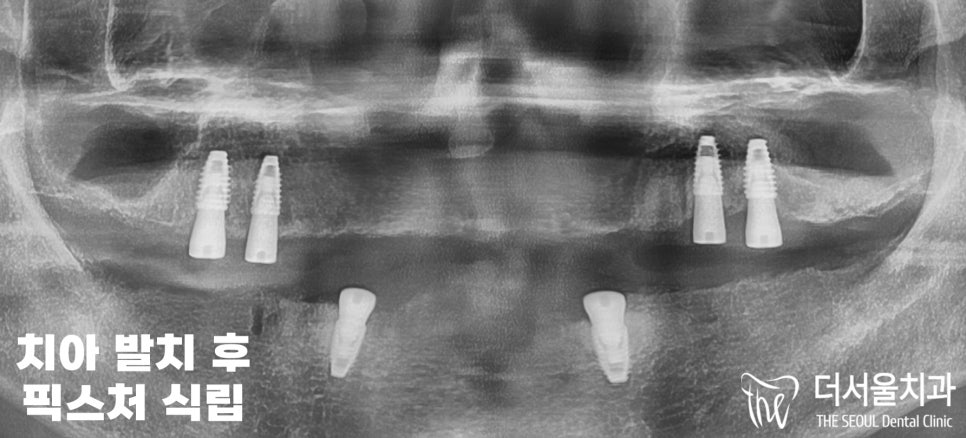

『픽스처 식립』

고정체 식립이 잘 이뤄졌는지

파노라마 엑스레이와 3D CT 촬영을 통하여

얼마나 깊게 단단히 심어졌는지

태평동치과 에서 확인했습니다.

위치나 각 등 계획했던 대로

잘 심어진 것을 볼 수 있습니다.